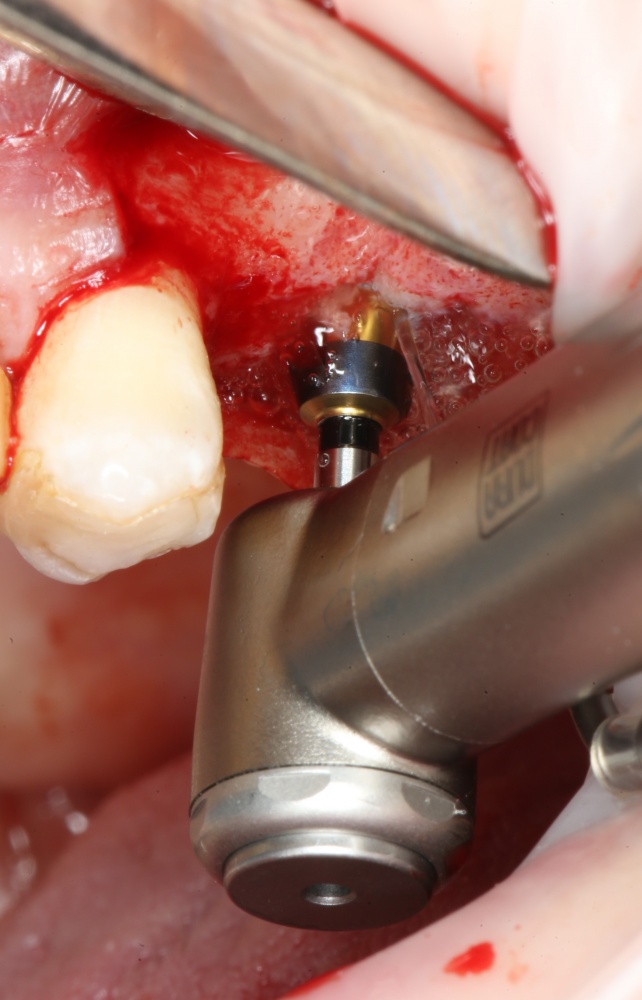

Приступаем к установке имплантата.

Кстати, комплект поставки не содержит ни заглушки, ни абатмента. А сам имплантат фиксируется на ключе простым заклиниванием платформы. Т. е. не слишком надёжно:

Если лунка подготовлена правильно, то имплантат проваливается в неё почти полностью: